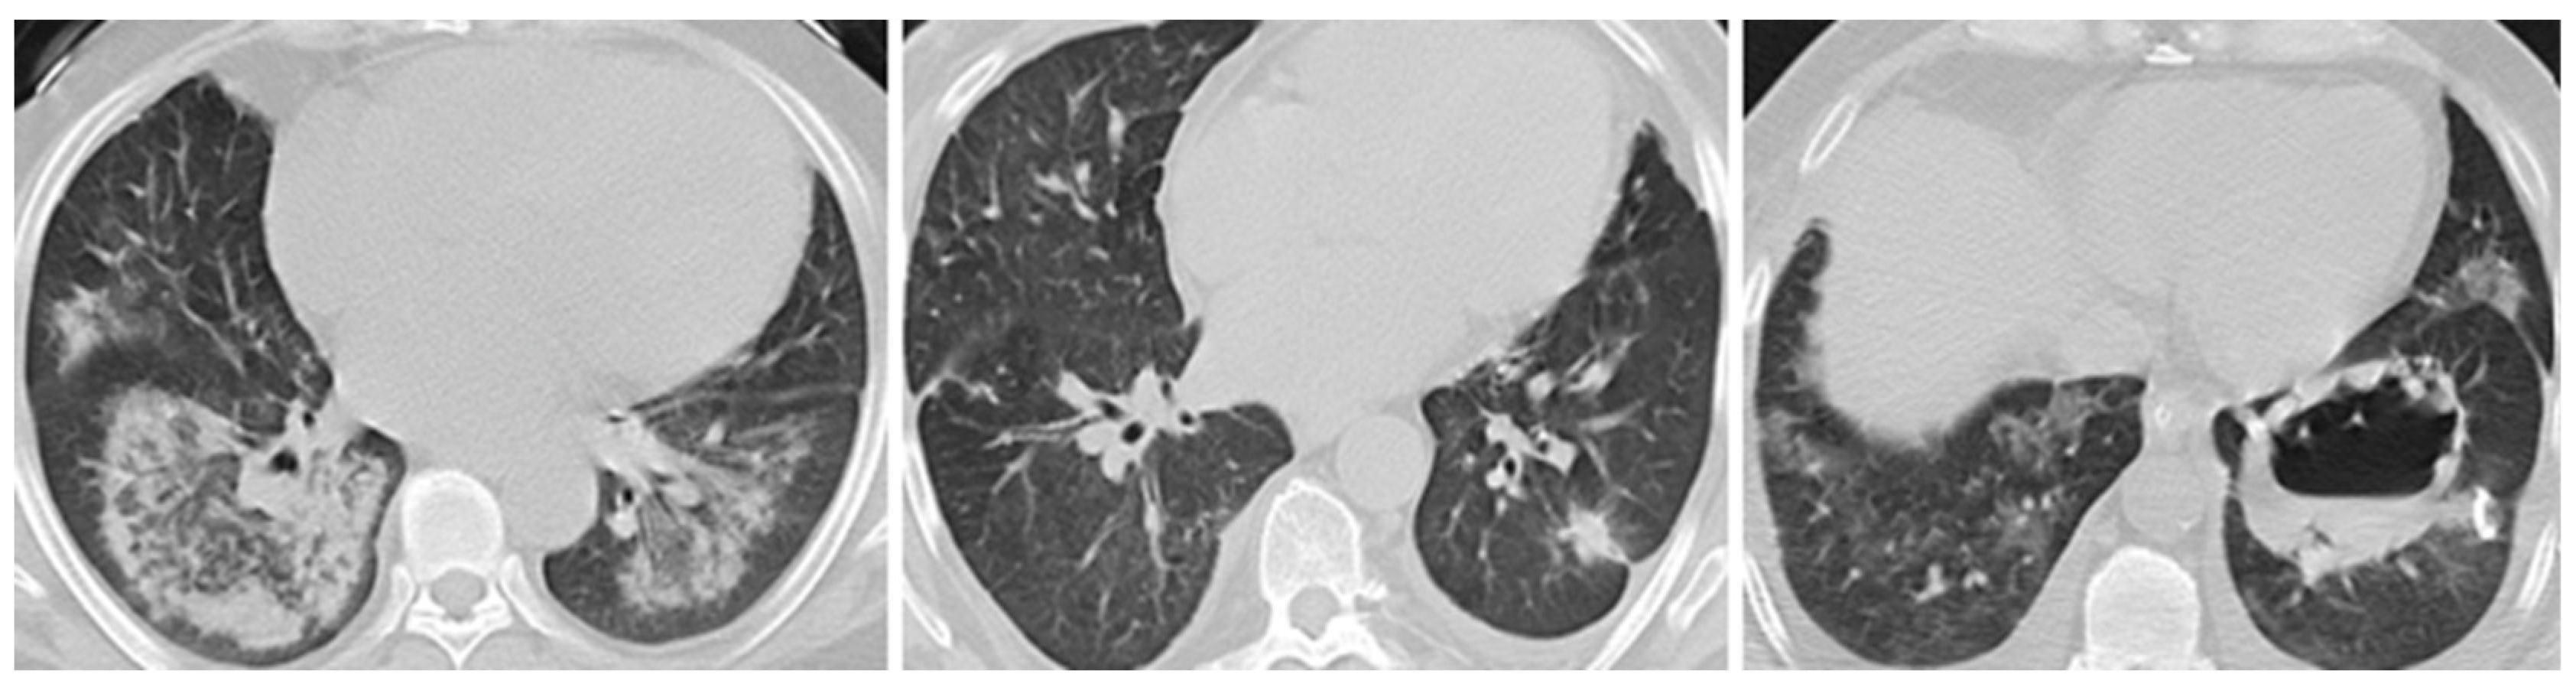

| Pulmonary involvement, n (%) | 56 (71.8) | 40 (90.9) | 12 (40) | 4 (100) | 0.002 |

| Pulmonary nodules, n (%) | 40 (51.3) | 26 (59.1) | 12 (40) | 2 (50) | 0.321 |

| Pulmonary infiltrates, n (%) | 32 (41) | 18 (40.9) | 10 (33.3) | 4 (100) | 0.744 |

| Cavitary lesions, n (%) | 20 (25.6) | 20 (45.5) | 0 (0) | 0 (0) | 0.002 |